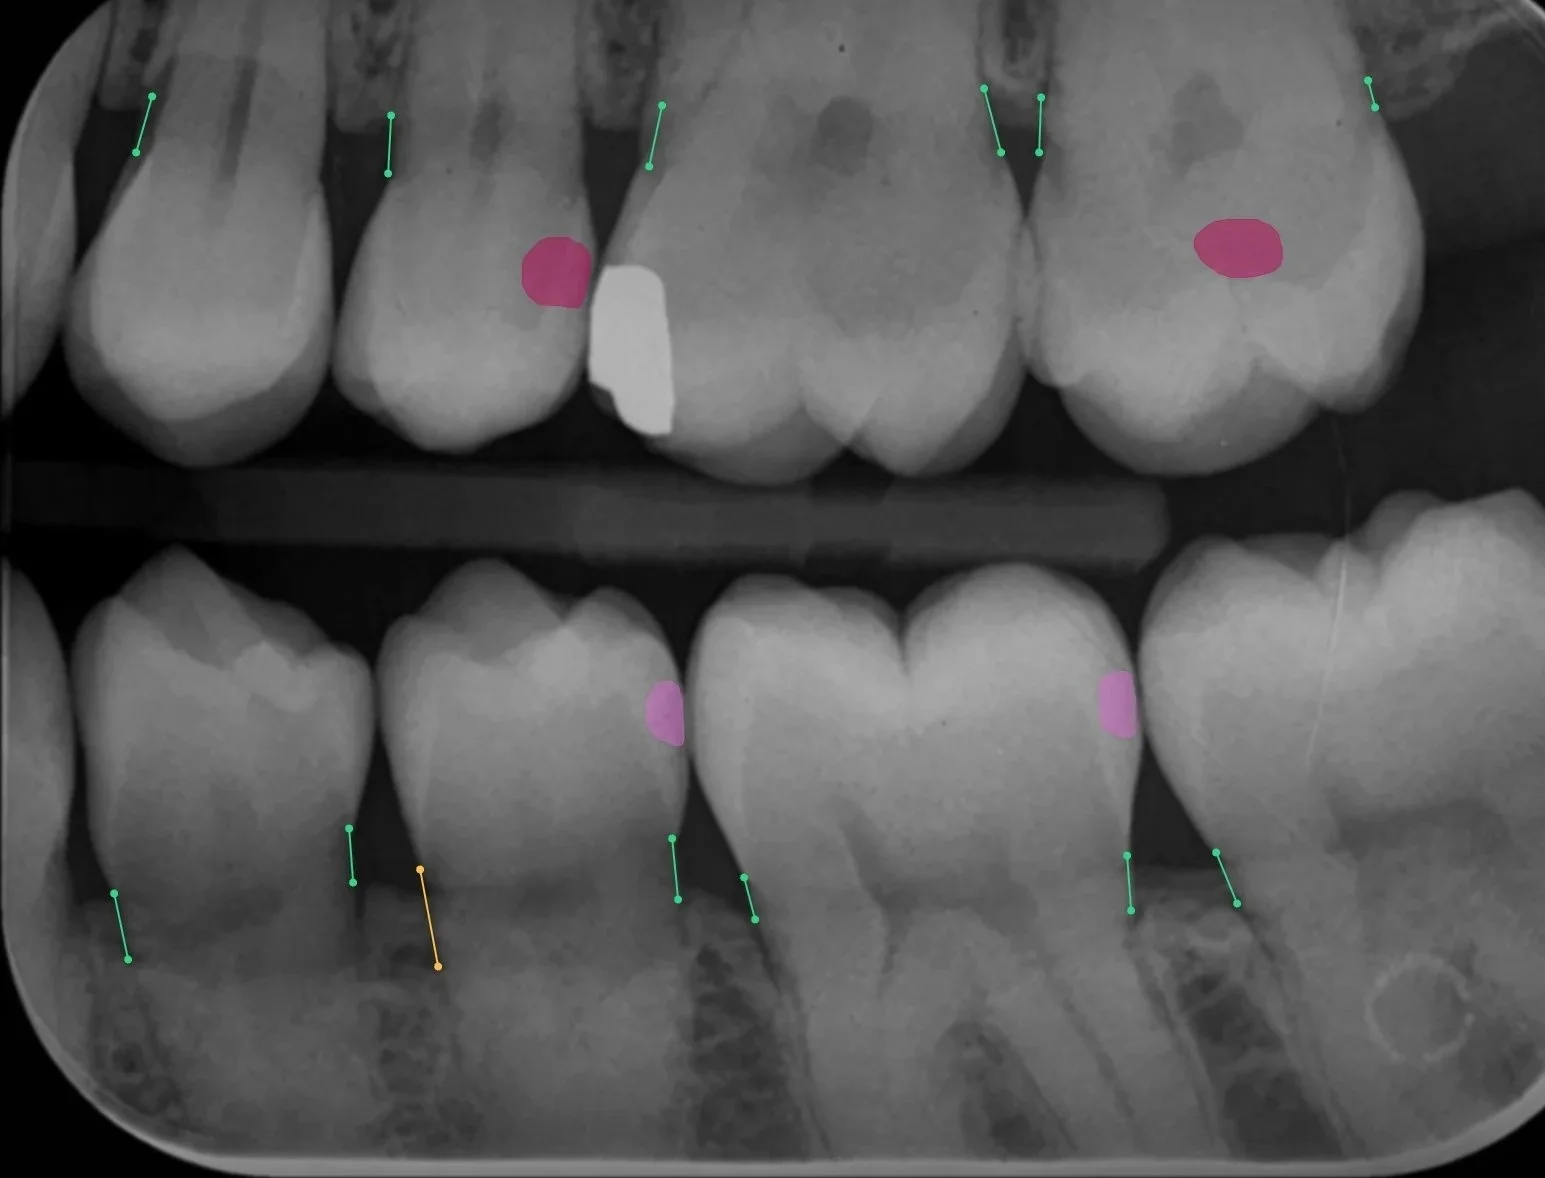

But at the end of the day, the goal stays the same: to understand your smile better and give you care that feels personal, precise, and genuinely thoughtful. We are so excited to be one of a handful of dental practices in Edinburgh offering Pearl dental AI assisted diagnostics on our radiographs allowing our clinicians not only to read radiographs but to have assistance in communication and diagnosis of findings from the latest in dental technology.

How Pearl Dental AI can assist in diagnostic imaging